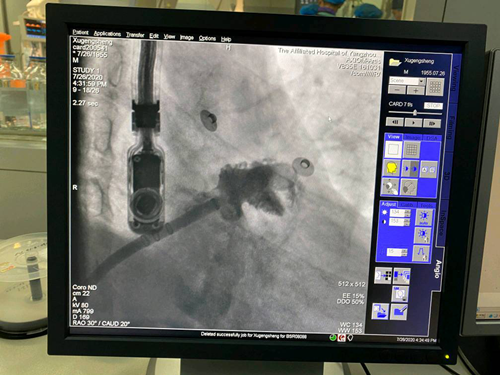

患者许某为男性,今年65岁。1年前被诊断为阵发性房颤,按医嘱口服抗凝药物达比加群酯。今年5、6月多次出现急性脑梗死。后入住我院心血管内科,经专家团队讨论,患者诊断为房颤所致的心源性脑栓塞。结合患者病史情况,专家们为其实施“房颤射频消融+左心耳封堵术”介入治疗。术后患者复查心电图为窦性心律,超声检查左心耳完全封堵,患者恢复良好。

据心血管内科副主任袁晓晨介绍,该患者采取一站式治疗方案,既恢复了其正常心律,又预防心源性脑卒中、全身性栓塞的发生。患者术后当日即可起床活动,手术并发症少、时间较短,适用于于老年人及不耐受外科手术的房颤患者。

据了解,“左心耳封堵术”是目前全球预防房颤患者卒中的治疗新趋势,它是通过导管将一个镍钛合金的左心耳封堵器安置在左心耳内,达到封闭左心耳的目的,从而预防左心耳内血栓脱落引起血栓栓塞事件的发生。同时,患者术后无需长期口服抗凝药物,不仅避免抗凝药出血并发症的发生,而且为患者节省医疗费用。